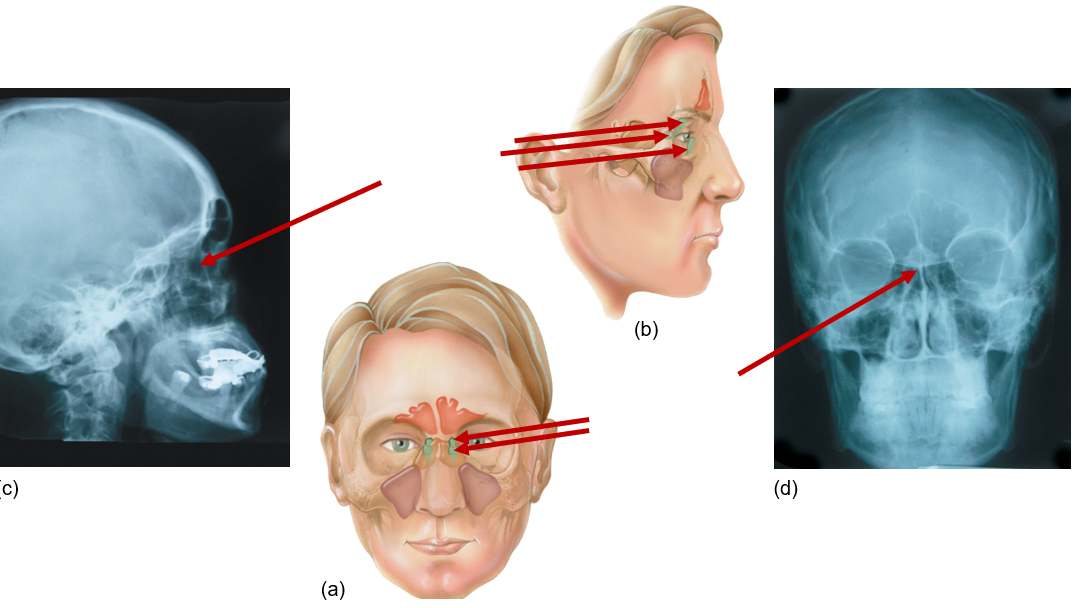

Frontal sinus

Front of head, above eyes

Sphenoid sinus

Behind eyes, near temples

Ethmoid sinus

Between eyes

Maxillary sinus

Next to nose, under eyes, maxilla